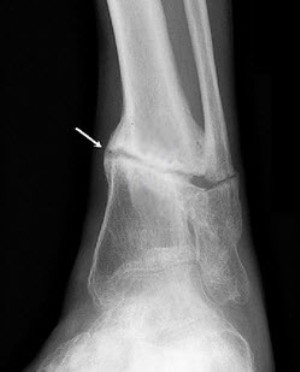

Диагностировать ложный сустав можно рентгенологическими методами. Рентгенограмма покажет два варианта псевдоартроза:

- Гипертрофический – это избыточное разрастание тканей кости в месте перелома при условии нормального кровоснабжения. Данная патология характеризуется быстрым ростом костной ткани в области перелома. Рентген покажет сильное увеличение расстояния между концами отломков.

- Атрофический – формирование псевдоартроза при недостаточном или отсутствующем кровоснабжении. На рентгенограмме заметны четкие границы краев отломков, которые удерживает соединительная ткань, хотя она не достаточно прочная, чтобы полностью обездвижить участок образования псевдоартроза.